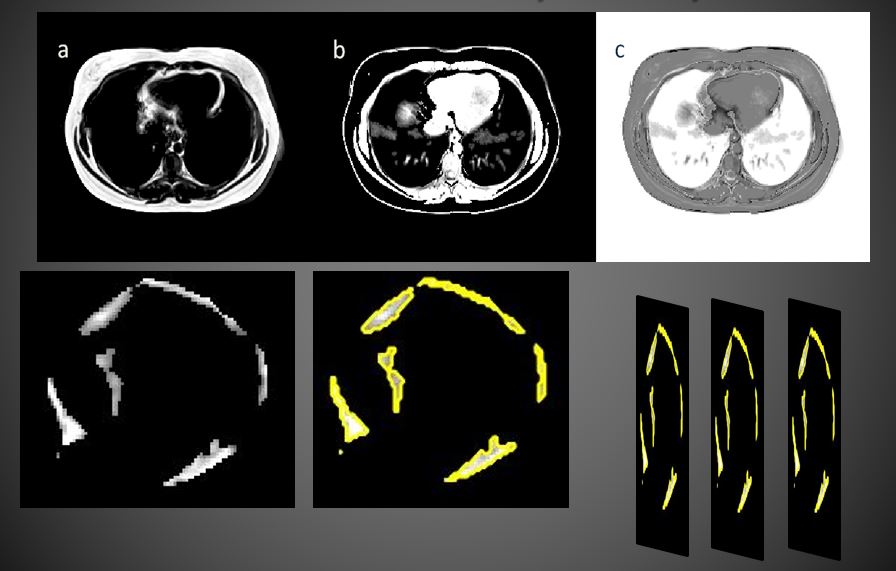

Obesity is a wide-ranging health problem and fat depots around the heart have been linked to the risk of cardiovascular disease. Magnetic Resonance Imaging (MRI) has emerged as the standard for quantifying epicardial fat for clinical studies but requires the analysis of a large number of images in a short time. We work on 3D segmentation of epicardial adipose tissue (EAT) and the development of tools to aid in studies of EAT and its relationship to cardiovascular disease and risk.